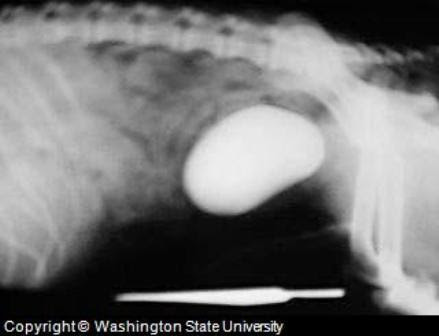

Bladder Cancer in Dogs | Canna-Pet® from canna-pet.com In the urinary system, the bladder is affected with cancer most commonly. The signs of bladder cancer can be similar to those seen with urinary tract infections. When i was sixteen years old, my family german shepherd, clancy, gave birth to six puppies on a cold december day.the next morning i leaped out of bed and ran to her whelping. Other signs of dog's bladder infection include painful urination, passing urine with a bad odor, pus or. While this cancer is very rare, it has a good prognosis if diagnosed in the early stages and treated accordingly. That's a cancer of the lymph system and bladder cancer. Urinary obstruction and bleeding are common signs. There are actually different kinds of bladder cancer that dogs can have;

An Overview to Canine Bladder Problems from www.dog-health-handbook.com While bladder cancer is relatively rare, representing an estimated 1 to 2 percent of all canine cancer, it does appear to be on the rise, affecting more than 50,000 dogs every year. However, when you hear of bladder cancer in dogs, it most likely refers to transitional cell carcinoma (tcc). This type of bladder cancer in dogs most often spreads to local or regional lymph nodes but can spread to any organ system via the bloodstream. One of the most surprising, and frankly, upsetting, things that we have learned from dr. Bloody urine, difficulty urinating, and licking of the area are all signs your dog might have a uti. Check your dog for other warning signs such as enlarged lymph. Symptoms will often improve initially with administration of antibiotics (as bladder infection is a common concurrent disease) but then recur a short time later. The most common type of malignant bladder tumors in dogs is transitional cell carcinomas (tcc), which usually affects the neck of the bladder in the area called the trigone.